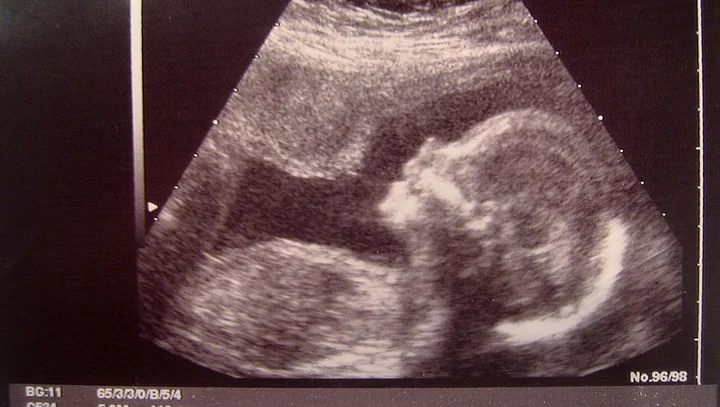

In what comes as a huge relief to the 14-year old girl, the medical panel at the Ahmedabad Civil Hospital on Thursday, gave its permission for the 25-week pregnancy to be terminated.

A panel of five doctors — four from civil hospital and a private practitioner — has given the nod for abortion.